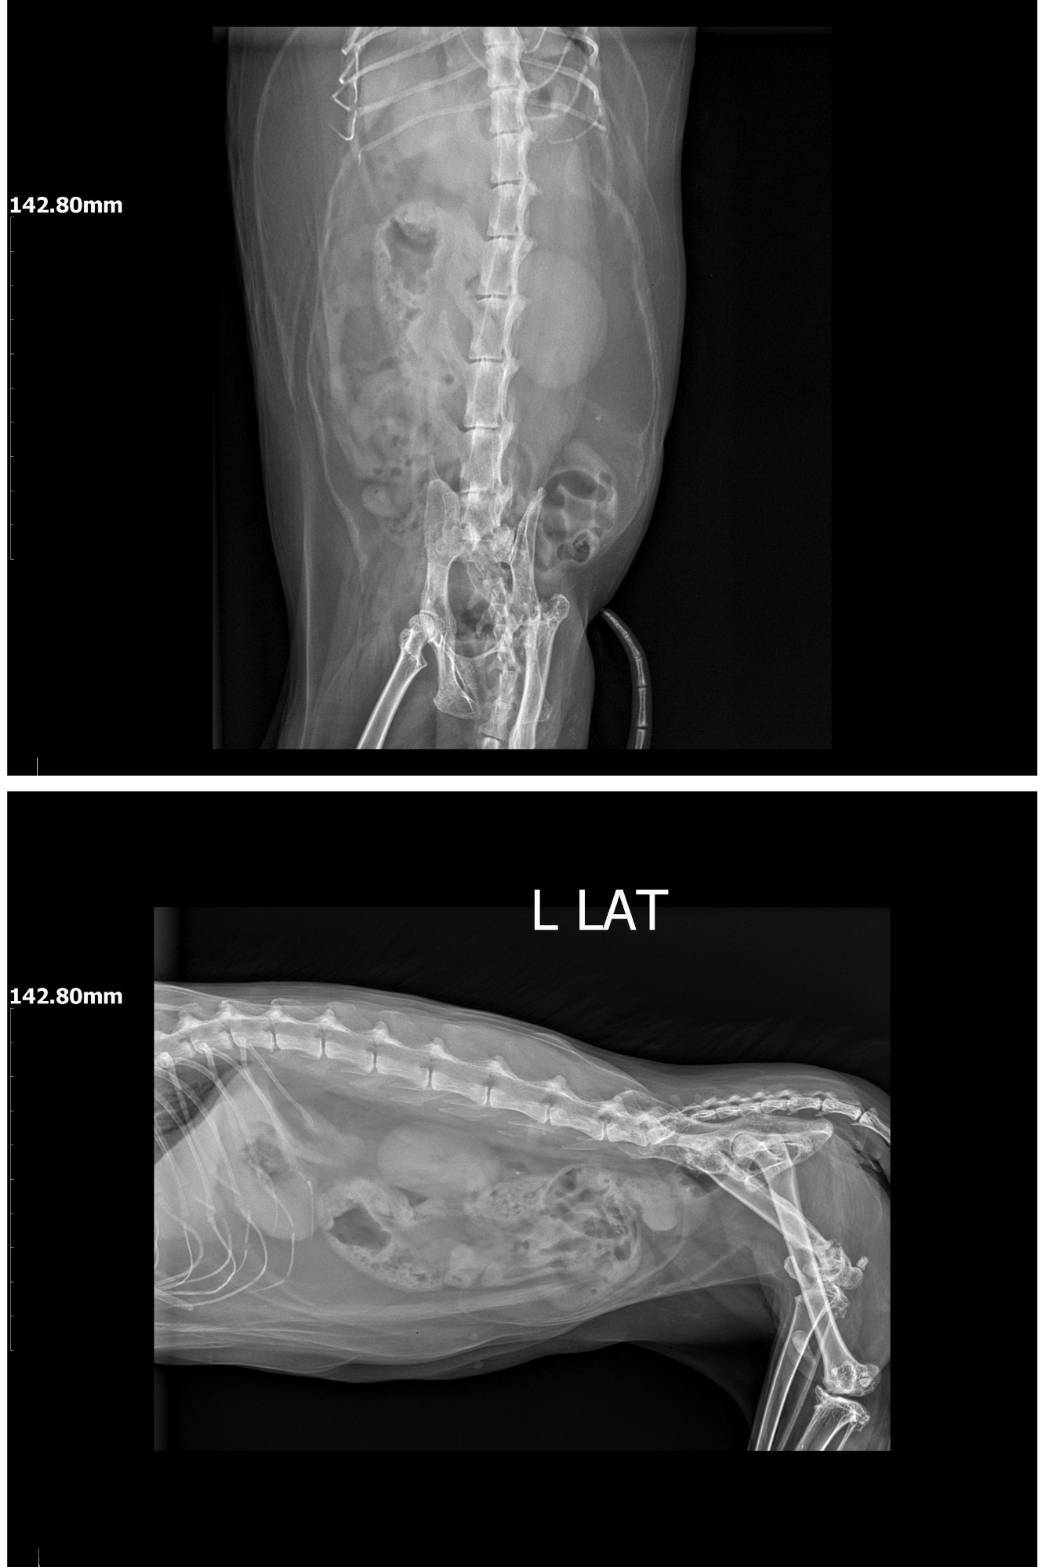

2025年7月1日沐恩回診,因疝氣摸起來變大詢問沐恩約診檢查,原本左側的腹壁疝氣已經定型,目前X光中只有小腸及脂肪疝出,降結腸及膀胱都沒影響,同時只要排便排尿正常就沒問題,但需要控制食量,因為乖妹的體重過重,如果體重沒控制持續上升,將會影響到脂肪突出疝氣的量。

目前X光中只有小腸及脂肪疝出,

降結腸及膀胱都沒影響,

同時只要排便排尿正常就沒問題,

但需要控制食量,因為乖妹的體重過重,

如果體重沒控制持續上升,

將會影響到脂肪突出疝氣的量。